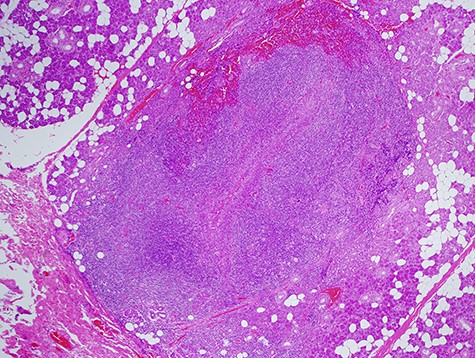

Histologically (Fig. 10), fibrosis and inflammatory granulation were seen. Inflammatory reaction of lymph nodes was observed. Epithelial cells could not be found in the slices.

Histological specimen of the final surgery. Inflammatory reaction of a lymph node inside of parotid the parotid gland was observed.